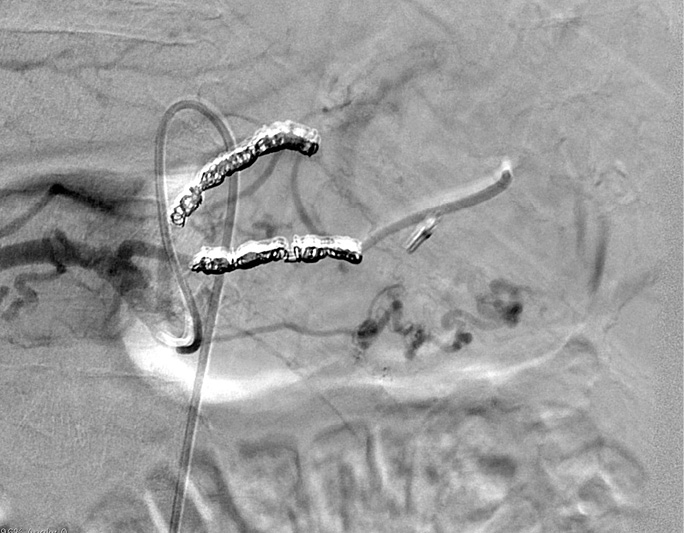

A 55-year-old male patient arrived at the Emergency Department of the Republican Vilnius University Hospital complaining of black stools and general weakness for only 1-day, tachycardia and low arterial blood pressure. UGIB was suspected. An extra esophagogastroduodenoscopy was performed. Arterial bleeding was observed from the posterior stomach wall in the border of the body/upper third of the stomach (Figures 1, 2). No pathological formations were visible in the mucosa. Dieulafoy’s lesion was suspected. The abdominal surgeon/endoscopist immediately started to stop the bleeding with adrenaline injection, but it was not enough. When we used endoscopic clip (Figures 3, 4). Bleeding was completely stopped. Patient’s condition was stabilized. But disease remained unknown. In order to reduce the risk of recurrent bleeding, we performed selective angiography of truncus coeliacus and embolization of the distal branches of arteria gastrica sinistra and some arteria lienalis branches, that feed formation through collateral blood flow (Figure 5). Large microspheres and pushing spirals were used for embolization (Figures 6, 7). The cause of bleeding still remained surely unknown. Now we suspected tumor. Only after by detailed strict anamnesis based on the patient’s life history, we conclude that the patient has a genetic disorder – Grönblad-Strandberg syndrome. According to our data, only four people suffer from this syndrome in Lithuania. Adjacent to this the patient had been operated for rectal cancer in the past, followed by ileostomy closure and abdominal wall hernioplasty for postoperative hernia. It is currently known that the patient has metastases in the liver and brain. The spread of cancer metastases, wide and severe comorbidities worsen the patient’s current condition, but despise these severe illnesses after proper and timely interventions, the patient lives without recurrent bleeding until now.

Figure 6. Transcatheter vascular embolization (partial)

Figure 7. Transcatheter vascular embolization (complete)

Advances (improvements) in catheter-based techniques (hydrophilic steerable wires, microcatheters) and newer embolic agents (materials) (coils, microcoils, cyclooxygenase-2 inhibitors, resorbable gelatin sponge, nonresorbable polyvinyl alcohol, tris-acryl gelatin particles, N-butyl2-cyanoacrylate glue, ethylene-vinyl alcohol copolymer) and wider availability of skilled interventional radiologists over the past three decades, made transcatheter arterial embolization (TAE) the effective first-line therapy for the management (controlling) of acute nonvariceal UGIB that is refractory to endoscopic hemostasis (one or two attempts) with low complication rate and decreased mortality [1, 8]. Unlike lower gastrointestinal bleeding (LGIB), patients with UGIB undergone endoscopic treatment prior to angiography, embolotherapy or surgery. Sometimes lesions are difficult to identify endoscopically, because they often stop bleeding spontaneously or severe bleeding present. The vascular supply to the stomach and duodenum is rich making successful embolization more challenging, but decreases the incidence of ischemia after embolization. Even localization of the bleeding site (for example, the angiografic extravasation of contrast into the bowel lumen or false aneurysm-like) without determination of the cause helps to treat bleeding and save the life. When a dual supply of the bleeding area is suspected, both arterial sources need to be embolized to assure that all the inflow ceases. Transcatheter intervention to control gastrointestinal bleeding takes two forms: the infusion of a vasoconstricting medication (intra-arterial vasopressin infusion) and the mechanical occlusion of the arterial supply responsible for the hemorrhage. Because of the high rebleeding rate with infusion or injection endoscopic therapy, embolotherapy has supplanted surgery in most centers as the treatment of choice for endoscopy-refractory UGIB with high success rate. The role of TAE is to selectively reduce blood supply at the source of bleeding while maintaining enough collateral blood flow to maintain intestinal viability. In general, bleeding in the esophagus and fundus of the stomach is treated by embolization of the left gastric artery (LGA). Bleeding in the body and antrum of the stomach may be controlled by embolization of either the gastroepiploic, right gastric or gastroduodenal arteries depending on the source of bleeding. Provocative mesenteric angiography is the use of thrombolytic, vasodilating, and anticoagulation medications to elicit active bleeding from a source that may have recently ceased hemorrhaging. Researchers advocate the practice of prophylactic embolization on the basis of endoscopic findings (for example, endoscopically marked with a metallic clip), even blind or empiric embolization in angiographic situations of absence of contrast extravasation, for preventing rebleeding in high-risk cases. To date, there has been limited number of controlled trials comparing angiographic embolization to surgery as a salvage procedure for failed endoscopic therapy [1, 8].

The collateral anatomy among vascular (feeding) branches from the celiac trunk or superior mesenteric artery varies widely in the pylorus-duodenum region. That’s why even embolization of the entire gastroduodenal artery (GDA) is frequently insufficient to stop the bleeding. To avoid “blind” embolization and enable guided transcatheter arterial embolization (TAE) of the correct selectively target vessel (branches) endoscopical marking ulcer (bleeding site/area) with a metallic clip can help even without extravasation of injected contrast medium [8, 9] during angiography minimizing the risk of recurrent bleeding [9]. But empiric or “blind” embolization is advocated in literature, because GIB has high rebleeding and mortality rates if untreated [8].